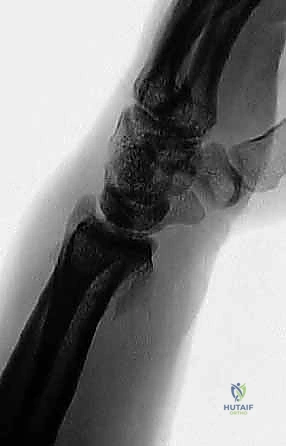

تُعد كسور الكعبرة البعيدة (Distal Radius Fractures) والزند الإبري (Ulnar Styloid Fractures) من أكثر الإصابات العظمية شيوعاً في العالم، وتمثل تحدياً كبيراً لجراحي العظام نظراً للتعقيد التشريحي والوظيفي البالغ لمفصل الرسغ. في الماضي، كانت هذه الكسور تُعالج إما بالجبس التقليدي الذي قد يؤدي إلى تيبس المفصل وضعف في قبضة اليد، أو بجراحات الفتح التقليدية التي تترك ندبات كبيرة، وتزيد من احتمالية تضرر الأنسجة الرخوة المحيطة، وتتطلب فترات نقاهة طويلة ومؤلمة.

أي كسر في هذه العظام، خاصة إذا امتد إلى داخل السطح المفصلي (Intra-articular fracture)، سيؤدي إلى اختلال الميكانيكا الحيوية للرسغ بأكمله. إذا لم يتم تسوية السطح المفصلي بدقة متناهية (بحيث لا يتجاوز الفارق 1 مليمتر)، فإن الغضروف سيتآكل بسرعة، مما يؤدي إلى ألم مزمن وخشونة مبكرة.

- كسر كوليس (Colles' Fracture): كسر في الكعبرة مع انزياح الجزء المكسور إلى الخلف.

- كسر سميث (Smith's Fracture): كسر في الكعبرة مع انزياح الجزء المكسور إلى الأمام.

- كسور داخل المفصل (Intra-articular): الكسر يمتد ليشق السطح الغضروفي للمفصل (وهنا تبرز الأهمية القصوى لاستخدام المنظار).

- تشوه شكلي واضح: في كسور كوليس، قد يأخذ الرسغ شكل "شوكة العشاء" (Dinner Fork Deformity) بسبب انزياح العظم.